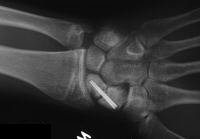

Clinical Example: Revision scaphoid nonunion with hardware removal, bone graft and two Herbert screws

This 19 year old had been treated elsewhere with an accutrac screw for a displaced scaphoid fracture. He was noncompliant with immobilization after surgery, and developed a painful nonunion.